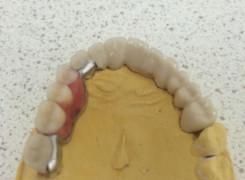

Pan Ryszard trafił do Naszego Gabinetu z jasno sprecyzowanym oczekiwaniem. Miał 84 lata i chciał odzyskać możliwość swobodnego spożywania posiłków oraz poprawienia sobie komfortu życia a także prosił aby przywrócić mu piękny uśmiech jakim cieszył się przed laty. Już na początku pierwszej rozmowy zastrzegł, że interesuje go wyłączenie rozwiązanie uzupełnieniem protetycznym stałym. Nie miał zamiaru użytkować żadnych protez ruchomych. Mając na uwadze powyższe wykonaliśmy Panu Ryszardowi zdjęcie pantomograficzne oraz badanie tomograficzne szczęki i żuchwy na postawie których zapanowywaliśmy Pacjentowi optymalne rozwiązanie – stałe uzupełnienie protetyczne w postaci 28 koron cyrkonowych zamontowanych do dwóch belek cyrkonowych które będą przymocowane do 16 implantów w konfiguracji 8 wszczepów w szczęcie 8 w żuchwie. Po omówieniu powyższego planu przystąpiliśmy do Wspólnej pracy której efekty w poszczególnych etapach prezentujemy poniżej.